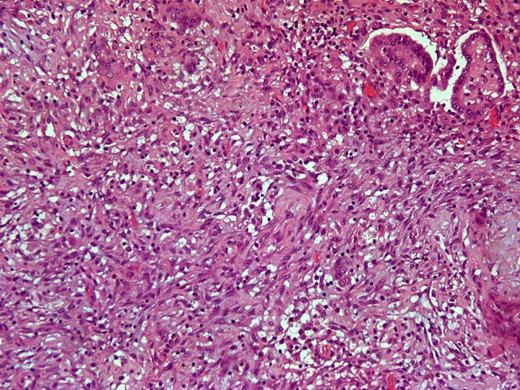

Here we report on a 32-year-old patient who presented at the Emergency Department complaining of acute abdominal pain accompanied by vomiting and diarrhea that had started three hours before. The patient was a para 2 and the latter delivery had occurred nine months before. She had been breastfeeding until 20 days before her ED visit and her menses had not yet resumed. Her medical history was unsignificant and she reported a laparoscopic ovarian cystectomy five years before, of which the histology report was not retrieved. She also had an ultrasound six months before, which described a pelvic multilocular cystic lesion of 11.4 × 8,6 × 12.3 centimeters, which remained untreated. The patient underwent an IV contrast—enhanced abdominal CT which demonstrated sizeable multilocular bilateral ovarian cystic lesions, of 18 cm and 15 cm in dimensions (in the right and left ovary respectively). (Figs 1 and 2). Her tumor markers were as follows (normal values are in parentheses): CA 15.3 = 20.53 U/ml (<25 U/ml), AFP = 1.08 ng/ml (<7 ng/ml), CEA = 0.63 ng/ml (<3.8 ng/ml), CA 125 = 110.40 U/ml (<35 U/ml), CA 19.9 = 50.06 (<34 U/ml), CA 72.4 = 6.74 (<6.9 U/ml). After the completion of preoperative investigations, the patient underwent and exploratory laparotomy. Frozen section revealed bilateral serous borderline tumors, therefore the patient underwent a total abdominal hysterectomy/bilateral salpingoophorectomy and epiplectomy. During surgical procedure astonishing remarks was the necrotized torsion of ovarian masses mimicking infiltrated ovarian neoplasm. (Figs 3–5). The final histology report confirmed the diagnosis of bilateral serous borderline tumors/atypical serous proliferative tumors, staged as pT1cNxMx or FIGO Ic. (Figs 6 and 7). Peritoneal fluid cytology showed mesothelial reactive lesions. The patient’s postoperative course was uneventful. The Multidisciplinary Team Meeting decided on adjuvant chemotherapy (four cycles of CarboTaxol; paclitaxel and carboplatin). Nine months after surgery, the patient remains alive and disease – free.

Intersection where the extrusion component is shown (H&E × 20).